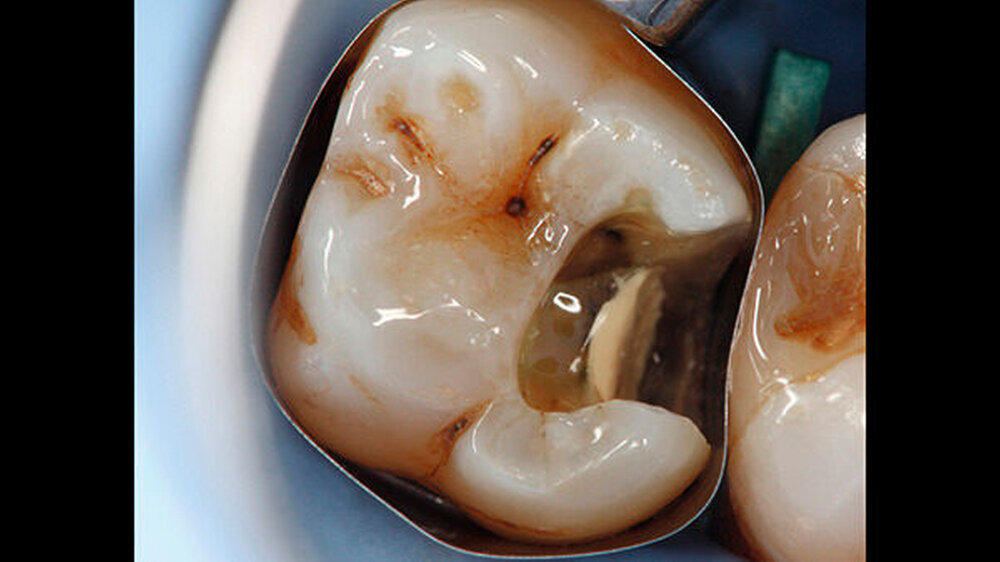

-Schnee war positiv. Die Behandlung wurde auf Wunsch des Patienten ohne Lokalanästhesie durchgeführt. Vor der Präparation erfolgte das Anlegen von Kofferdam an den Zähnen 24 bis 27. Zunächst wurde mit rotierenden Diamantschleifern unter Wasserkühlung von okklusal ein Zugang zum Defekt geschaffen. Der distale Kavitätenbereich wurde mit oszillierenden Instrumenten präpariert (SonicFlex, KaVo) (Abbildung 2). Dabei wurde die Kavität so zierlich wie möglich gestaltet.

Anschließend erfolgte die Kariesexkavation mit Rosenbohrern unter optischer Kontrolle mit einem OP-Mikroskop. Die Kavität wurde im Verlauf der Exkavation mehrmals mittels FACE (fluoreszenzgestützter Kariesexkavation, SIROinspect, Sirona) auf Residualkaries überprüft [Buchalla W et al., 2013].

Bei der vollständigen Kariesentfernung kam es nicht zu einer Freilegung der Pulpa (Abbildung 3). Anschließend wurde eine Metallmatrize (HaweTofflemire Matrize, Kerr Dental) angelegt und verkeilt. Die Kavität wurde gereinigt und getrocknet.